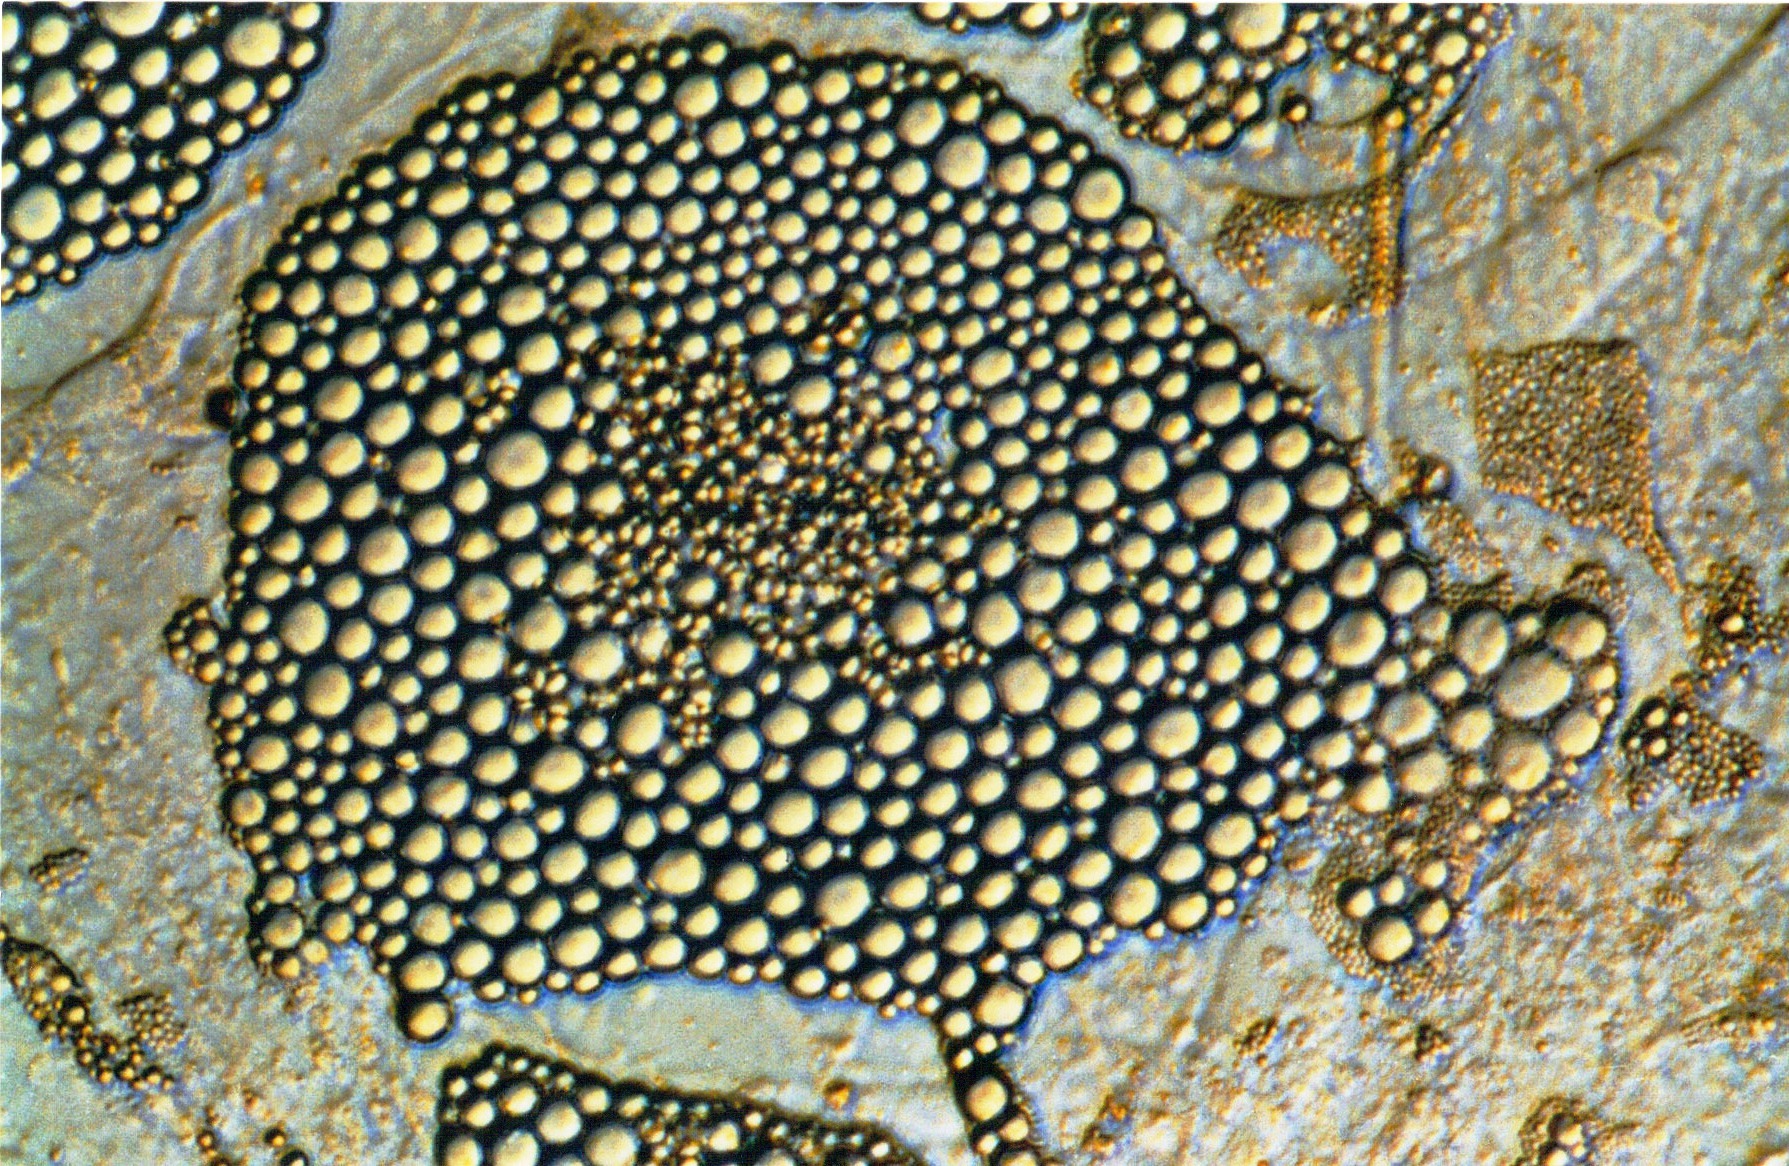

Εικ. 2γ-1: Απεικόνιση δύο τυπικών λιθοστρωτόμορφων περιοχών, από δύο σταδίων καλλιέργεια φυσιολογικού μυελού 35 ημερών. Οι C.A. είναι κλώνοι αιμοποιητικών κυττάρων που εντοπίζονται κατά κανόνα κάτω από τα κύτταρα του στρώματος. Είναι κύτταρα μεγάλα, σκοτεινά, μη φωτοδιαθλαστικά στο μικροσκόπιο αντιθέτου φάσεως, και συχνά πολυγωνικoύ σχήματος. Η τυπική διάταξη των κυττάρων δημιουργεί χαρακτηριστικό σχηματισμό δίκην λιθοστρώτου. - Μεγέθυνση: x400 εικόνα